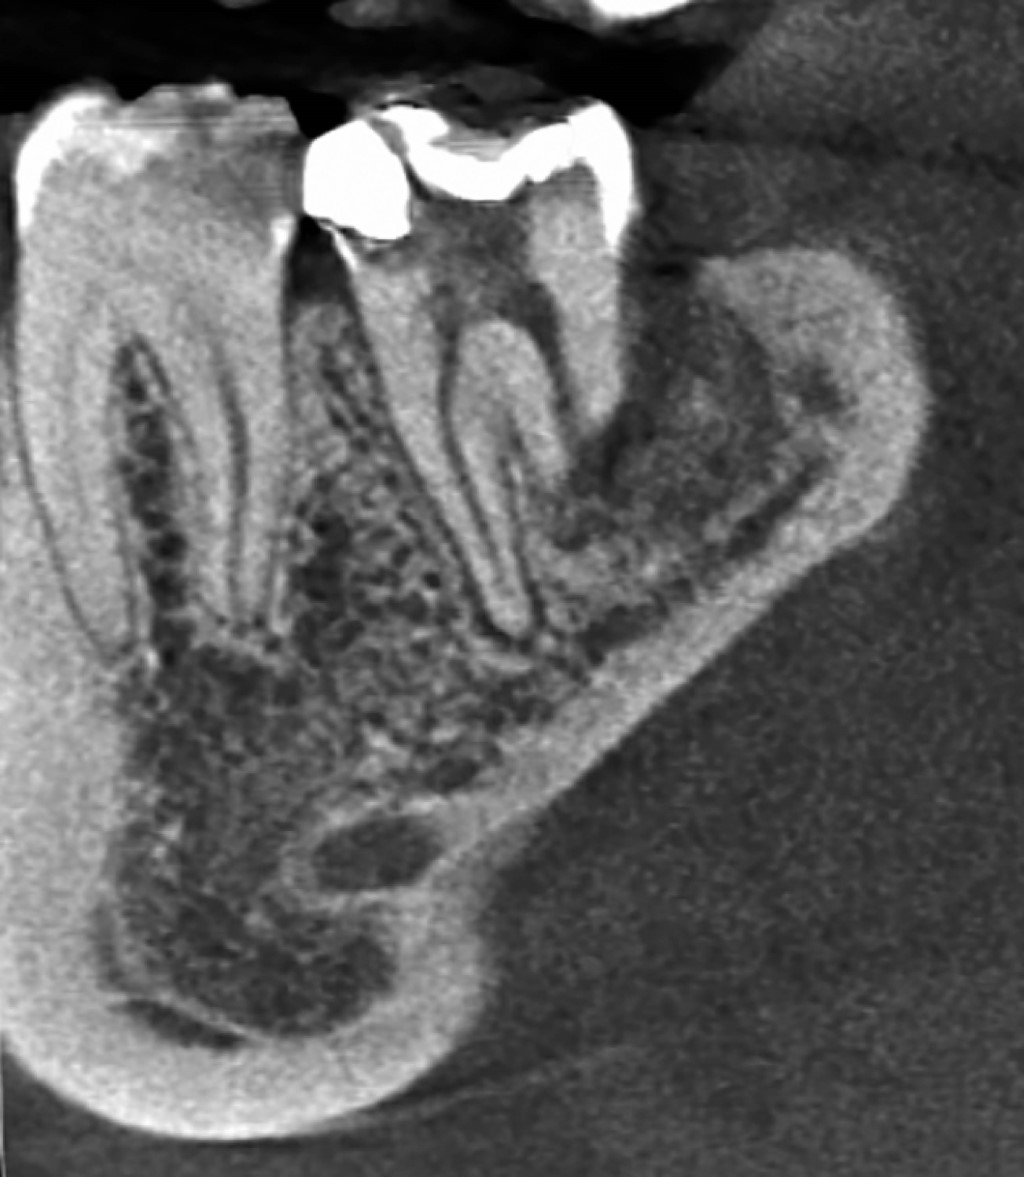

Las imágenes de reconstrucción 3D muestran pérdida de cortical vestibular en la zona del tercer molar, de forma redondeada, compatible con la forma de la corona del tercer molar extraído previamente, así como reabsorción de los tercios medio y apical de la raíz distal del segundo molar, observando que la reabsorción no se presenta de forma simétrica, la pared lingual de la raíz se extiende aproximadamente al tercio medio, no así la pared vestibular de la misma raíz que solamente está presente hasta el tercio coronal (Figuras 3 y 4).

La proyección coronal de la tomografía comprueba lo anterior, además muestra un conducto distal amplio que se extiende solamente hasta el tercio coronal radicular (Figura 5).

Por su parte, en la proyección sagital se observa que la pared mesial de la raíz distal termina aproximadamente en el tercio medio radicular y la pared distal tiene su nivel en el tercio coronal (Figura 6).

Con la información previa podemos asegurar que el conducto distal se encuentra permeable y tiene un diámetro amplio, características que lo hacen candidato para utilizar en él la herramienta del software OnDemand3D denominada Endoscope, que permite hacer una reconstrucción en 3D del interior del conducto radicular, con esto comprobamos que efectivamente la amplitud del conducto distal es considerable y que debemos tener precauciones al obturarlo, para que el material de relleno no salga hacia el espacio periodontal (Figuras 7, 8 y 9).

Figura 3

Figura 4

Figura 5

Figura 6

Figura 7

Figura 8

Figura 9